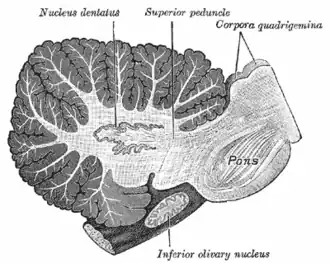

Olivopontocerebellar atrophy can be used as a pathological term to describe degeneration of neurons in specific areas of the brain – the cerebellum, pons, and inferior olivary nucleus.[49] OPCA is present in several neurodegenerative syndromes, including inherited and non-inherited forms of ataxia (such as the hereditary spinocerebellar ataxia known as Machado–Joseph disease) and MSA, with which it is primarily associated.[49]

| Sagittal section through right cerebellar hemisphere. The right olive has also been cut sagittally. | |

Historically, many terms were used to refer to this disorder, based on the predominant systems presented. These terms were discontinued by consensus in 1996 and replaced with MSA and its subtypes,[61] but awareness of these older terms and their definitions is helpful to understanding the relevant literature prior to 1996. These include striatonigral degeneration (SND), olivopontocerebellar atrophy (OPCA), and Shy–Drager syndrome.[62] A table describing the characteristics and modern names of these conditions follows:

| Sporadic olivopontocerebellar atrophy (OPCA) | characterized by progressive ataxia (an inability to coordinate voluntary muscular movements) of the gait and arms and dysarthria (difficulty in articulating words) | MSA-C, "c" = cerebellar dysfunction subtype |